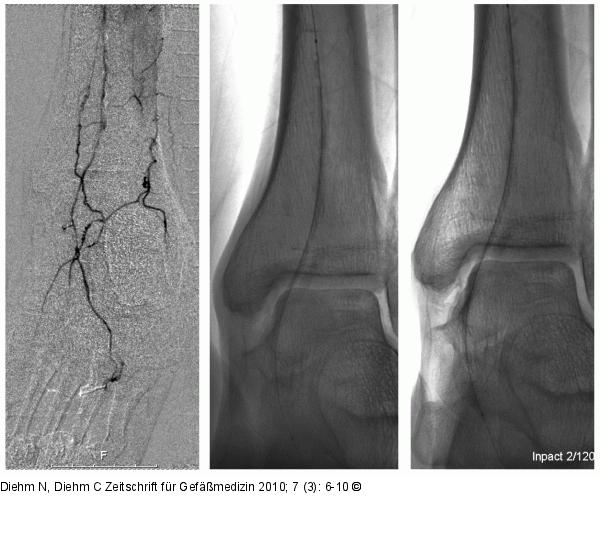

Abbildung 2: A. dorsalis pedis - A. plantaris pedis Angiographische Darstellung einer diffus stenosierten A. dorsalis pedis und A. plantaris pedis. Nach Vordilatation mit 2/120-mm-Ballon wird die restenotische Läsion mittels 2/120-mm-Paclitaxel-beschichtetem Ballon vordilatiert. |

Angiographische Darstellung einer diffus stenosierten A. dorsalis pedis und A. plantaris pedis. Nach Vordilatation mit 2/120-mm-Ballon wird die restenotische Läsion mittels 2/120-mm-Paclitaxel-beschichtetem Ballon vordilatiert. |